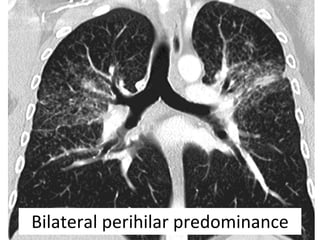

Bilateral perihilar predominance